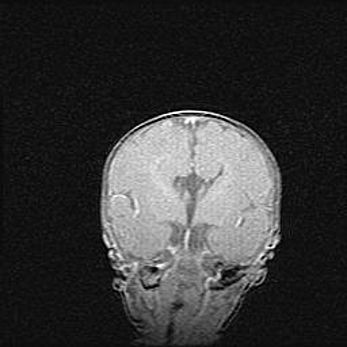

Церебральная ишемия II.

Возраст: 5 дней

Вес: 3400 г

Пол: женский

Окружность головы: 35 см

Срок гестации: 39 недель

Церебральная ишемия – это заболевание, характеризующееся недостаточностью (гипоксией) либо полным прекращением (аноксией) снабжения мозга кислородом по причине закупорки одного или нескольких сосудов. Это приводит к  что метаболическим расстройствам различной степени тяжести в тканях головного мозга, развитию коагуляционных некрозов и гибели нейронов.